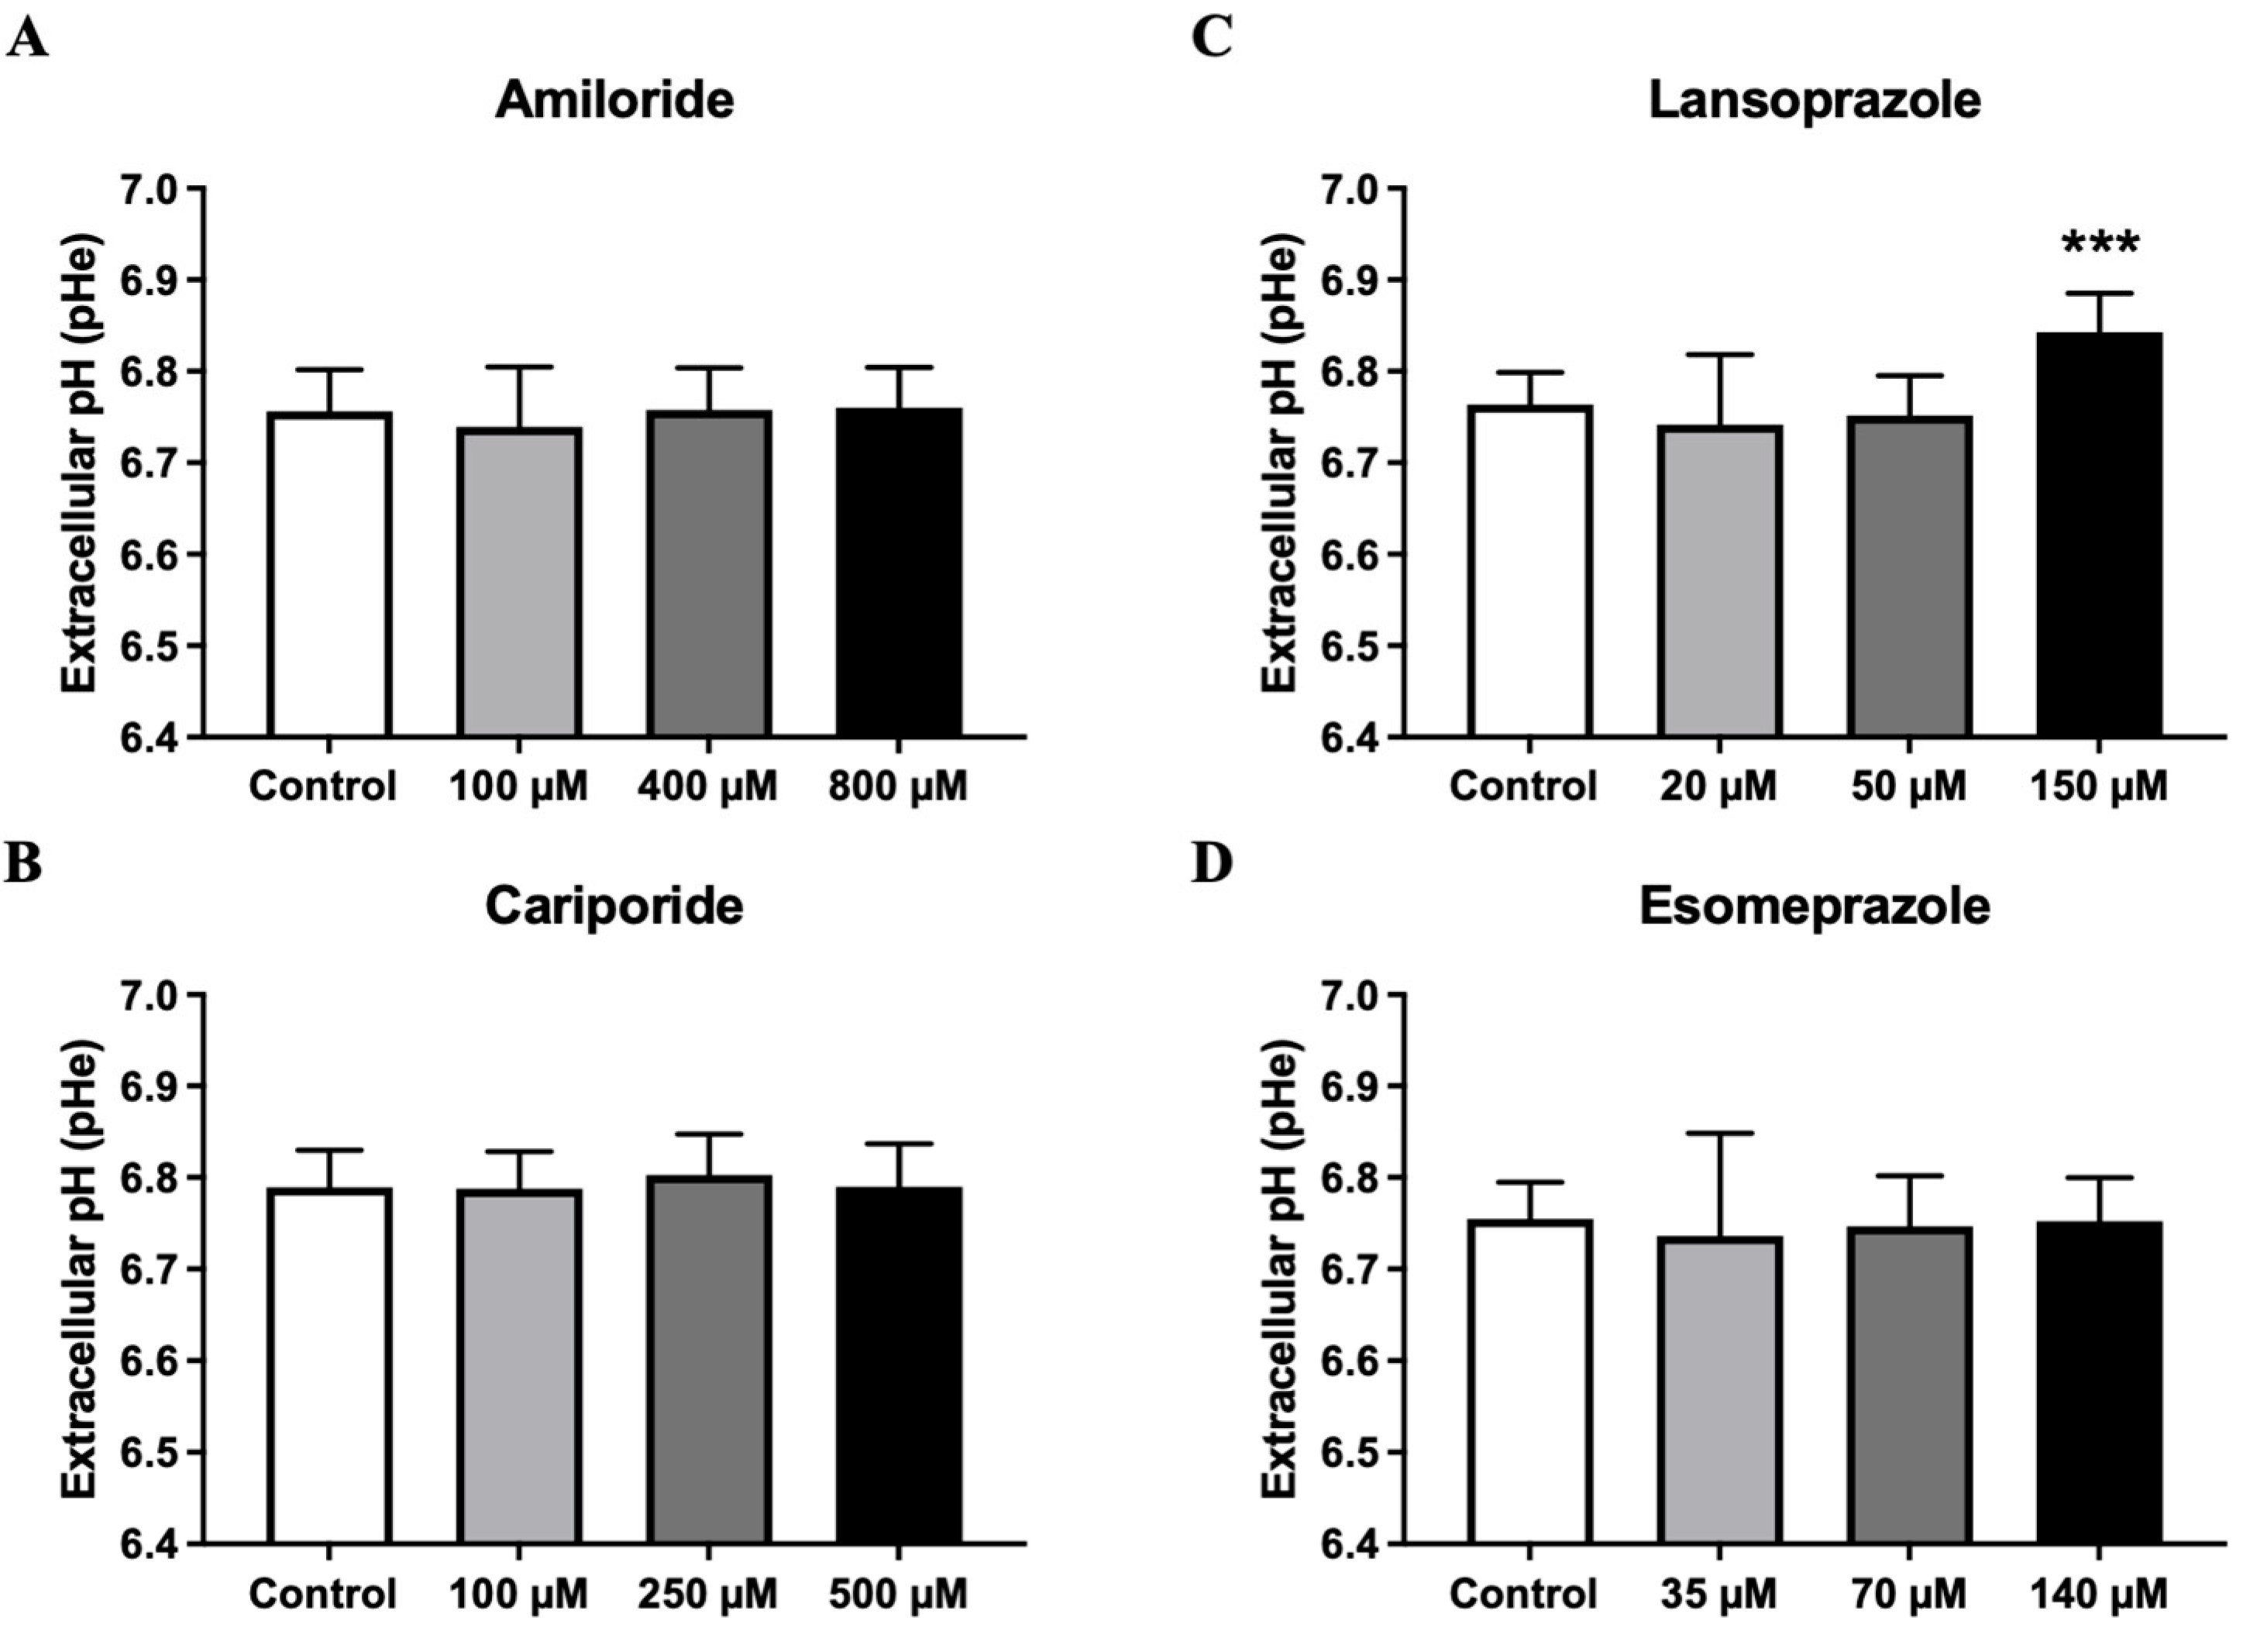

2.5. In Vitro Extracellular pH Measurements

3.2. Lansoprazole Induces a pH Increase in the Extracellular Medium of 4T1 Metastatic Breast Cancer Cells